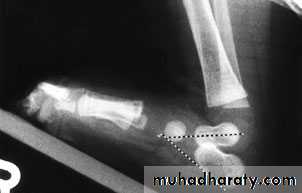

X-ray:

Lines can be drawnthrough the long axis of the talus parallel to its medial border & aline passing in the longtudinal axis of calcanium parallel to its latral border should de 20-40 digree